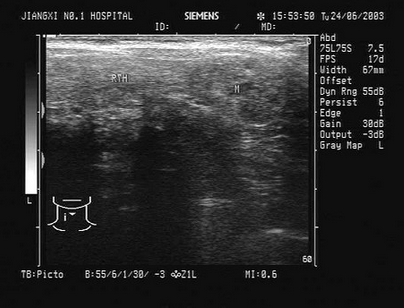

10、单项选择题

女,40岁,有时右上腹隐痛2年余。结合超声声像图,最可能的诊断为()

A.肝血管瘤

B.肝脓肿

C.小肝癌

D.转移性肝癌

E.肝囊肿